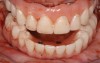

Fig 13. An All-on-4 approach was used to treat both arches with interim immediate and eventual definitive restorations.

Figure 13

This is an unfortunate mindset in that current advances in protocol and technology can result in significant advantages in addressing some or most of these concerns. The patient shown in Figure 12 may serve to illustrate this point. She had a destroyed maxillary dentition, a less-compromised but highly unesthetic mandibular component, and a single goal: to be able to "smile at my grandchildren again." In consultation with her and her family, it was decided that a double-arch fixed implant approach would most realistically address her esthetic goals and provide her with the desired prosthetic result. She was 102 years old at the time of initial consultation. Using a staged operating-room approach, provisional restorations were initially delivered, followed by subsequent definitive hybrid final restorations. She was able to use these comfortably for the next 6-½ years (Figure 13 and Figure 14).